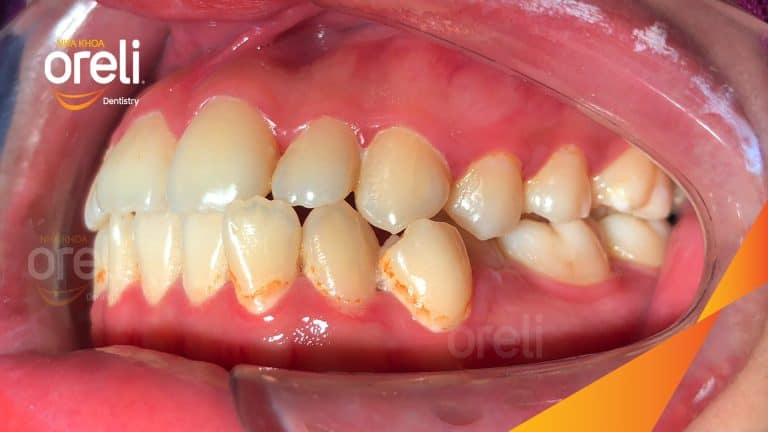

Ca niềng chỉnh chen chúc sai khớp cắn hạng 3 móm nhẹ – Kết quả thực tế ở Oreli Niềng răngChen chúcMóm Xem thêm